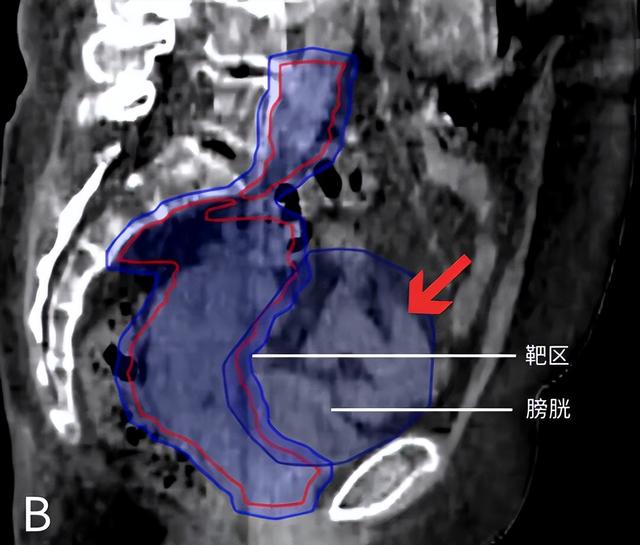

图为宫颈癌患者的矢状位图像。图A为计划CT,憋尿良好,肠道被推挤出盆腔;图B为治疗时的CBCT图像,憋尿较差,更多的肠道(红色箭头指示部分)进入照射区域。